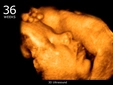

23 haftalık gebelik, hamileliğin ikinci trimesterinin sonlarına yaklaşıldığı bir dönemi ifade eder. Bu süre zarfında, hem anne hem de bebek için birçok önemli gelişim ve değişiklik yaşanmaktadır. Bu makalede, 23 haftalık gebelik dönemindeki fiziksel ve duygusal değişimlerin yanı sıra, bebeğin gelişimi, anne adayının sağlığı ve dikkat edilmesi gereken hususlar ele alınacaktır. Bebeğin Gelişimi23 haftalık gebelikte bebek, hızla büyümeye devam etmekte ve birçok önemli gelişim sürecinden geçmektedir. Bu dönemde, bebeğin gelişimiyle ilgili bazı önemli noktalar şunlardır: